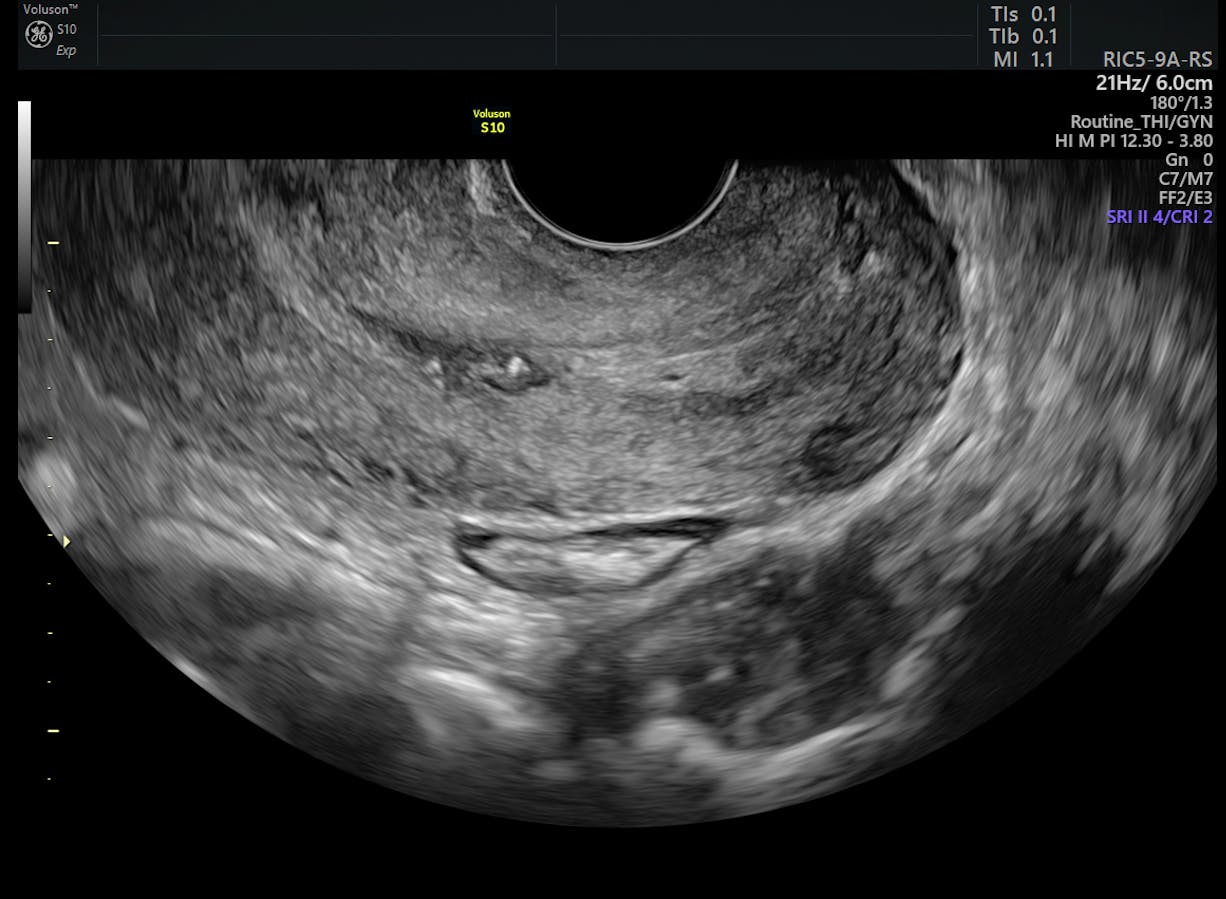

Colposcopy Information Jo S Cervical Cancer Trust from www.jostrust.org.uk The most common signs and symptoms are. Cervical cancer develops in a woman's cervix (the entrance to the uterus from the vagina). Your doctor or nurse will let you know how often you should be tested. Care guide for cervical cancer. Pap tests, also called pap smears, detect precancerous changes or cancerous cervical cells. However, most women with dysplasia do not develop cancer. Your healthcare provider will do a pelvic exam to check for problems with your cervix, uterus, and ovaries. Cervical cancer is cancer that starts in the cervix, the narrow opening into the uterus from the vagina.